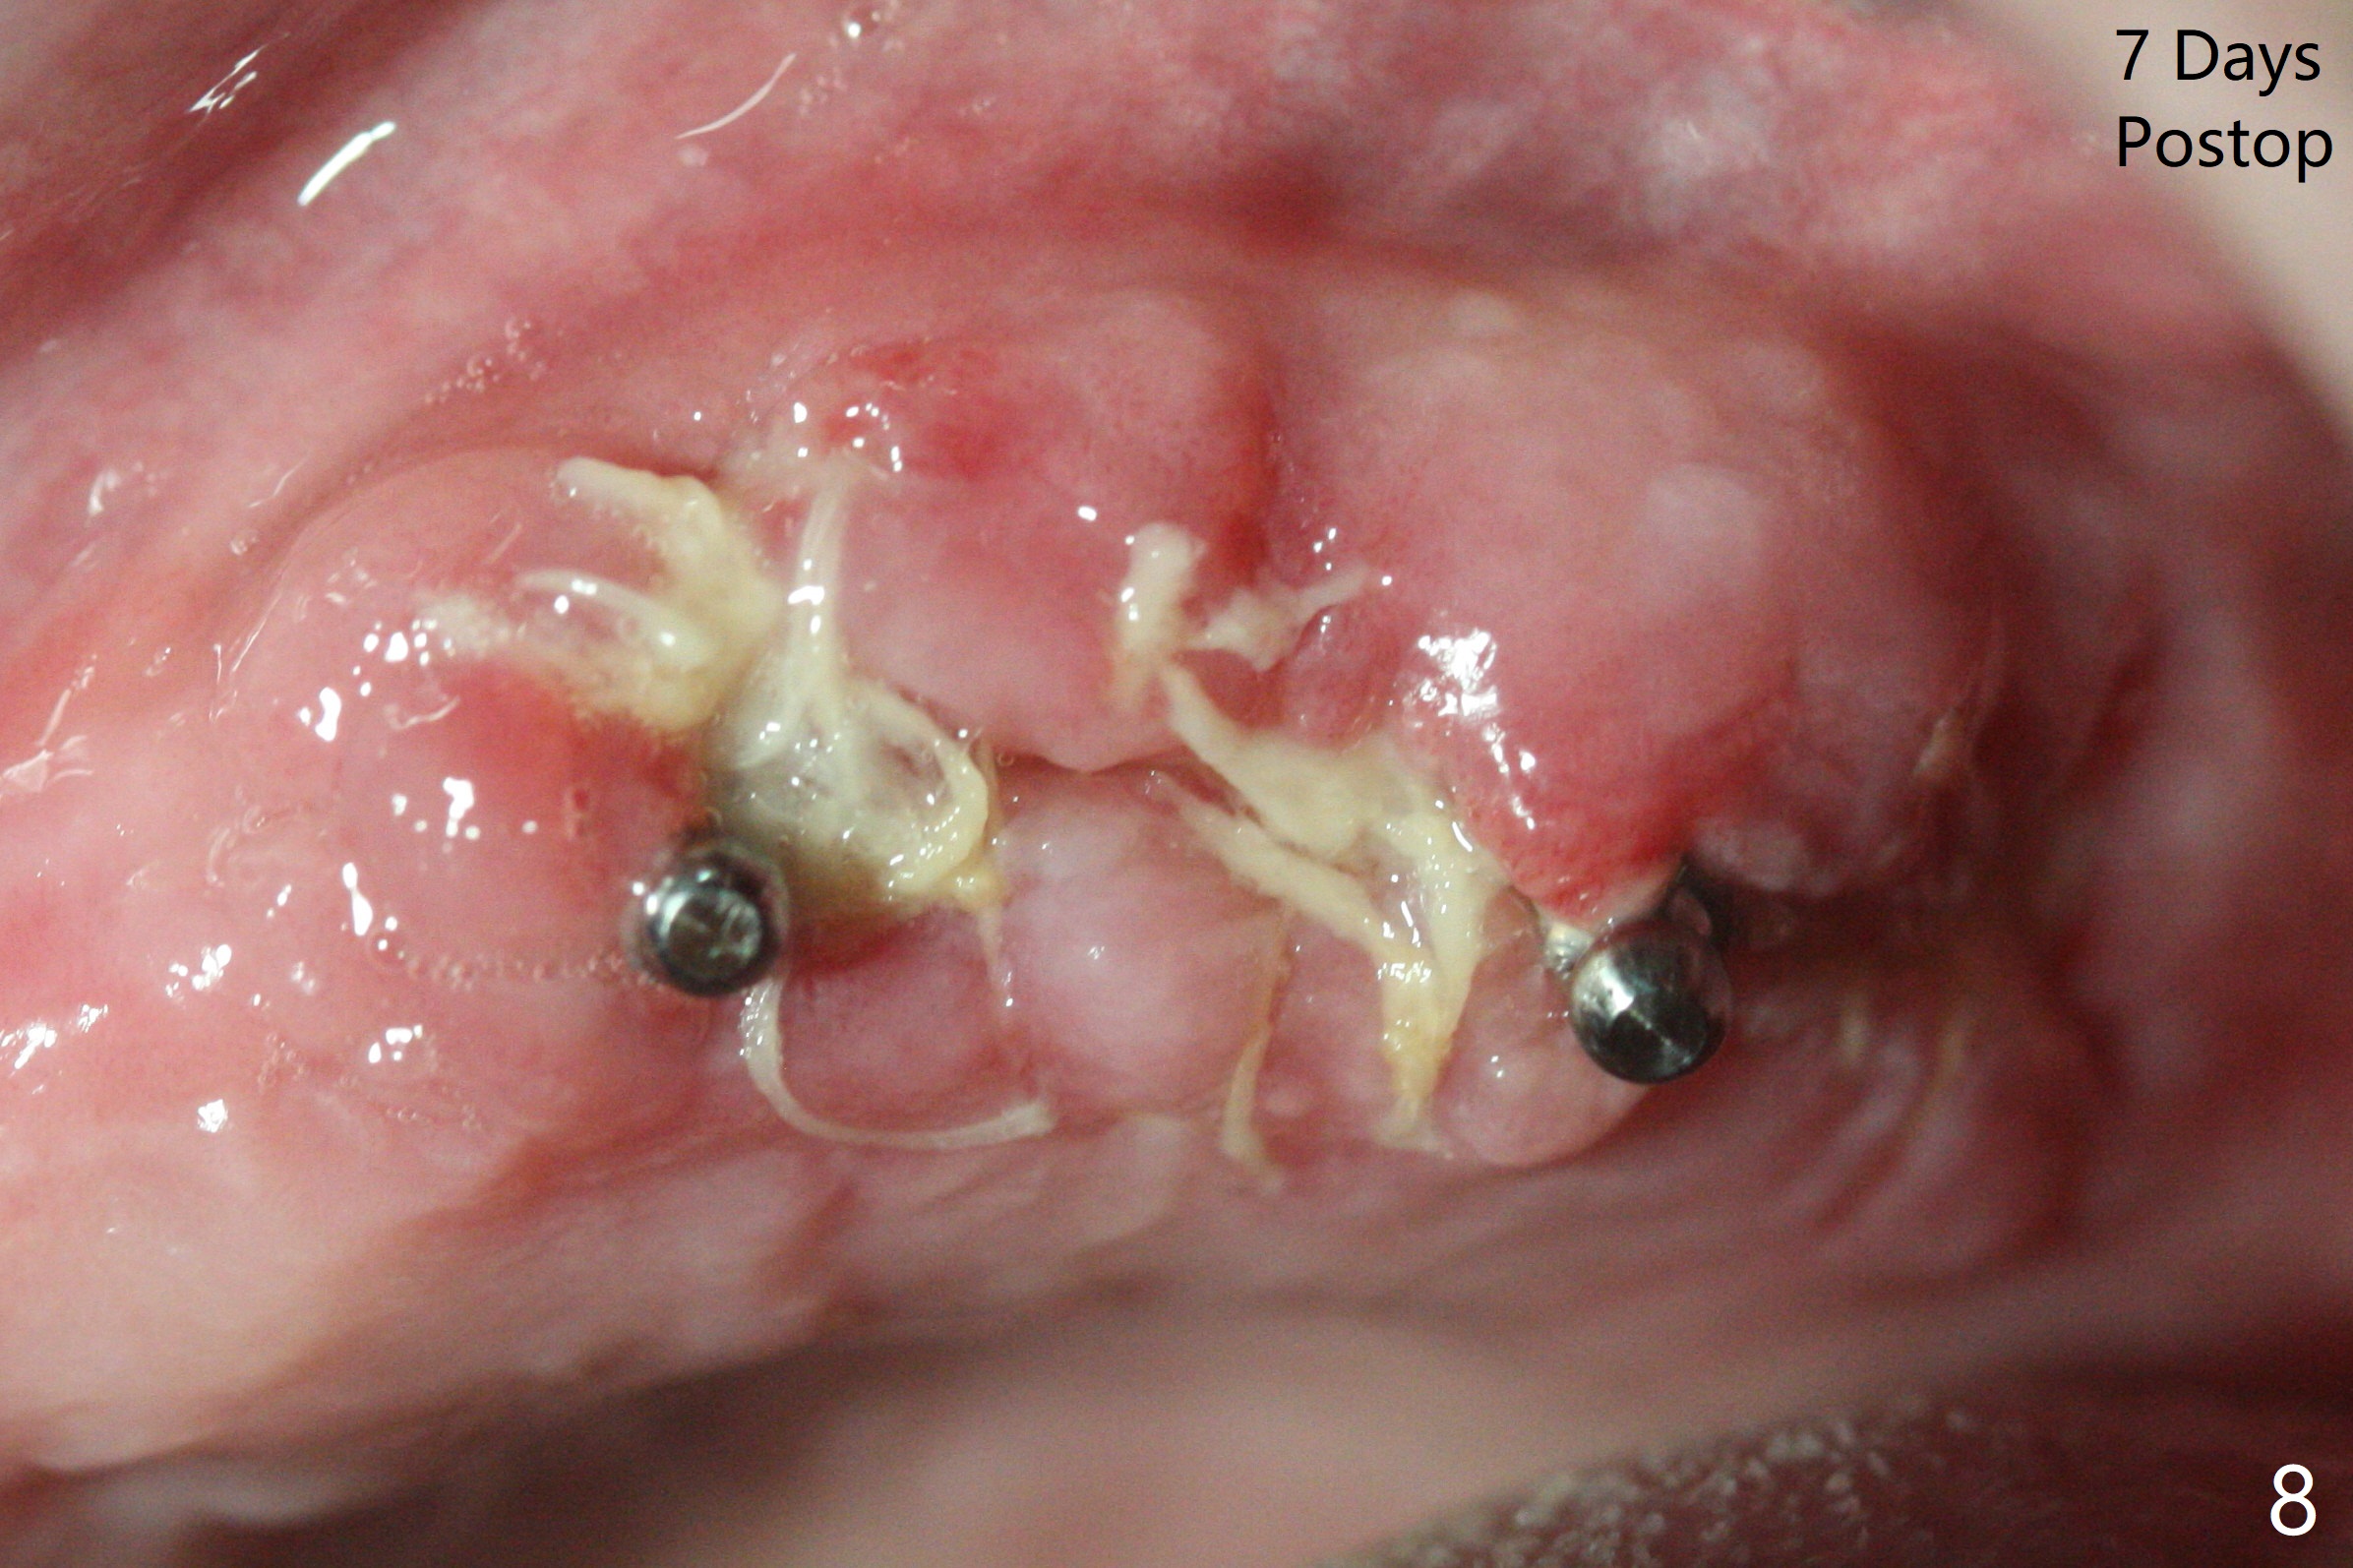

Osteotomy at #13 starts blindly (no incision or tissue punch) with bone expanders. After insertion of parallel pins, intraop CT shows that it is palatal with apparently buccal low bone density (Fig.1); the osteotomy for implant (Fig.2 green) should be shifted buccal and tilted mesial (red, parallel to #11) with incision. In contrast the position, trajectory and depth (Fig.3 <) of the initial osteotomy are acceptable at #11. The implant will be placed as it is (Fig.4). After taking a postop PA (Fig.5), the implant at #11 is placed a little deeper to make sure its slightly subcrestal placement (including distal incision at #11). Following placement of 3.5x4 and 3 mm ball abutments at #11 and 13, cortical allograft with PRF is placed around the implants, especially buccal (Fig.6,7 <). After suturing, the profile of the ball abutments is too low for RPD retention. Due to gravity other than bone density, the number of ball abutments for the maxilla should be more than for the mandible. Soft reline is done to the patient's satisfaction. The retention of the upper RPD after soft reline is satisfactory without pain 7 days postop (Fig.8). The implant at #13 is loose nearly 3 months postop (Fig.9 *: bone loss). The implant is removed while the ball abutment is untightened; the sinus floor is present. It appears that a longer and larger implant is necessary; a 4.5x10 mm dummy implant is unable to be seated deep or achieve primary stability (Fig.10). After sinus lift with 3 mm Bicon osteotome without bone graft, the dummy implant accomplishes the 2 tasks mentioned above (Fig.11). However there is no corresponding definitive implant in stock. Implant system needs to be changed; with a change in implant driver, the depth control is lost. The final implant is placed deep (Fig.12). With back up, stability is lessened; a healing screw is placed; with collagen plug, the wound is sutured (Fig.13). The wound heals 1 week postop (Fig.15). The RPD is soft relined. Retention from the ball abutment at #11 is apparently critical. The RPD and #11 implants (4 months postop) are stable, while the wound at #13 heals 1.5 months postop (Fig.15). There is space around the implant 5.5 months postop (Fig.16 *). The 5x10mm SM implant is found to be loose upon uncover and removed. After debridement, 5.3x8 mm SM and 5.5x9 mm IBS dummy implants are inserted without stability, while 6x9 mm definitive one with stability (Fig.17). Cortical allograft is placed in deficiency areas (*). The osteotomy has no roof (sinus floor), but the sinus membrane is intact. Small amount of bone graft (Fig.18 *) is placed before implantation. There appears to be bone around the new implant (Fig.19 (3D sagittal section) *).